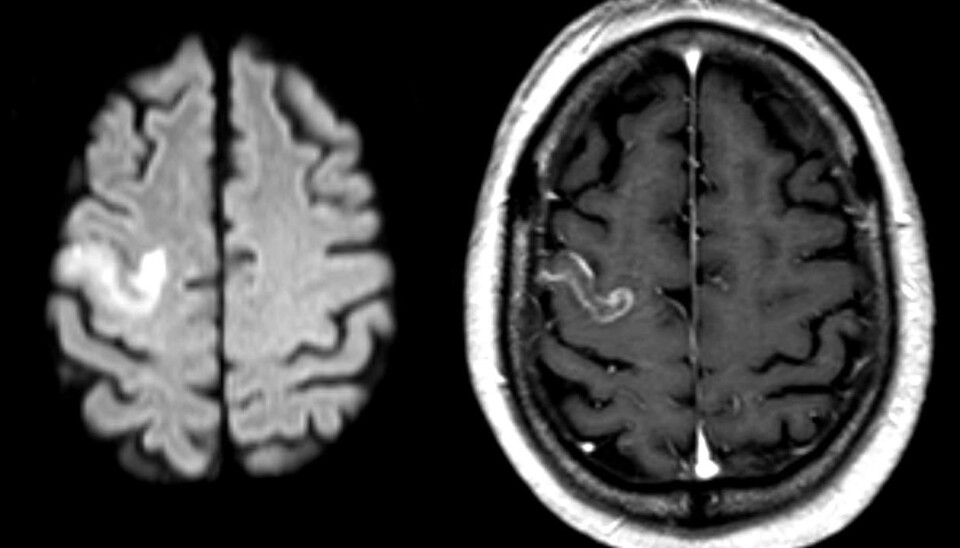

The article deals with a study, carried out in Germany, observing a group of stroke patients with language difficulties. They were all brain scanned using the fMRI technique as an important part of the analysis. An essential part of the research was done by the Bergen fMRI Group at UiB.

The patients were scanned several times by an fMRI-machine, both before and during language training. During a multimodal analysis, the researchers studied how the networks of the brain were activated.

The multimodal analysis involves analysing MR scan images of the extent of the brain damage in stroke patients whilst studying brain activity using fMRI scans.

“Using this method, it is possible to find the localisation of the damage, the size of the damage and how the activation patterns in the neural networks are related,” Specht explains.